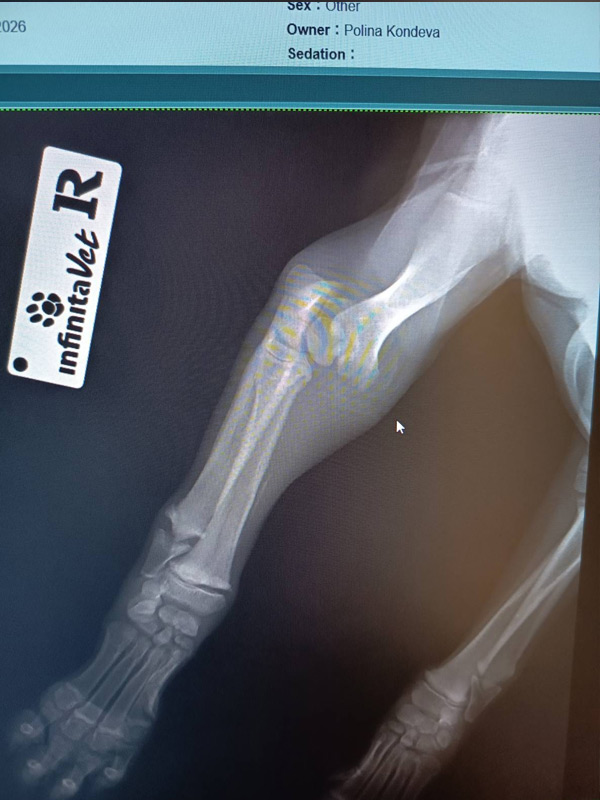

Was ursprünglich nicht absehbar war: Sowohl ihr Vorderbein als auch ihr Hinterbein mussten operiert werden.

Das rechte Hinterbein wurde mit einer Platte stabilisiert und ist aktuell noch in einem schützenden Verband. Hier geht es zu Luca’s Video.

Ihr Vorderbein konnte nur mithilfe eines Fixateur externe (Fix Ex) versorgt werden – eine aufwendige, aber notwendige Maßnahme, um ihr überhaupt eine Chance auf eine schmerzfreie Zukunft zu geben. Dieser Fix Ex wird nach einiger Zeit wieder entfernt.